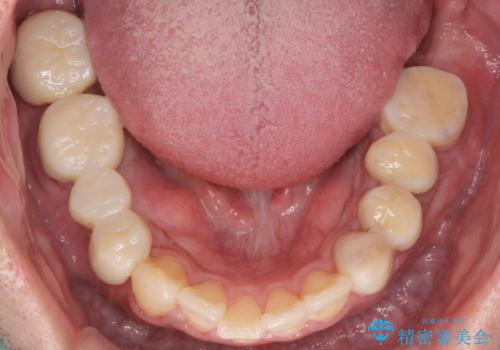

その後、インプラント治療、セラミック治療を行いました。

一度治療するはを全て仮歯に変えて、歯茎を整えてからセラミックを装着しました。

適合の良い被せ物、インプラントが入りました。